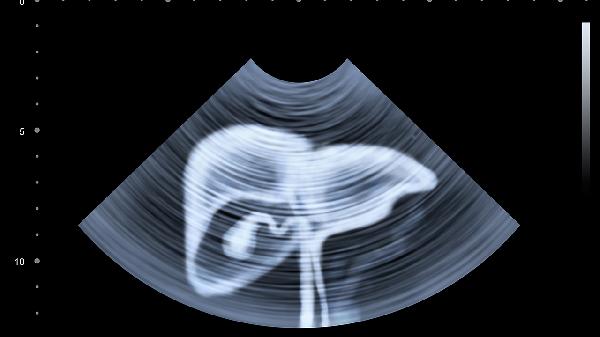

一、晚餐时间影响肝脏排毒效率

肝脏在晚上11点到凌晨3点进入高效排毒期。如果晚餐吃得太晚,肝脏不得不分出一部分精力来消化食物,导致排毒功能打折。长期如此,肝脏负担加重,毒素堆积,肝功能指标自然下降。把晚餐提前到6-7点,给肝脏留出3-4小时的消化时间,你会发现肝功能指标逐渐改善。